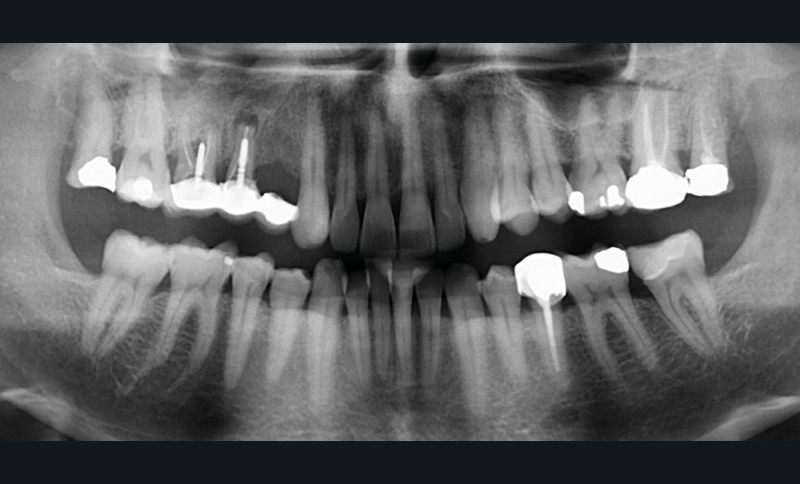

À la radiographie panoramique, on constate une lésion apicale sur 15 et une atteinte inter radiculaire sur 16 ainsi qu’une légère rotation de 21 sans gêne pour le patient.